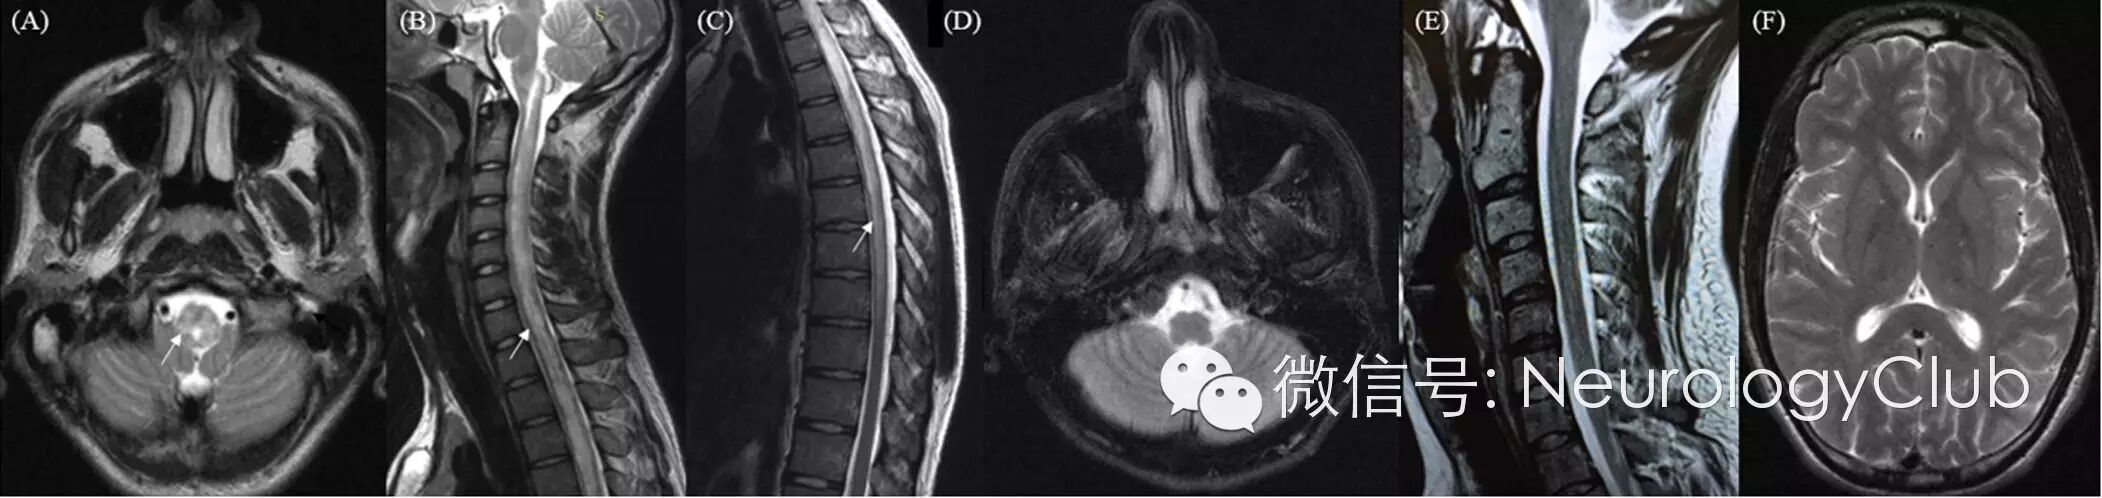

27岁男性,进行性加重的头痛伴恶心呕吐,视物模糊,下肢无力及尿失禁5天。既往史与家族史无殊。查体:血压230/140mmHg,双侧高血压性视网膜病变伴视乳头水肿,下肢轻瘫,腱反射活跃。血化验提示肌酐(3.4mg/dL)和尿素氮(145mg/dL)水平升高,血清抗水通道蛋白-4 IgG抗体,病毒学及风湿免疫学检测阴性。脑脊液常规及生化无殊,单纯疱疹病毒(HSV-1与2)PCR阴性。头及脊髓MRI提示脑干至中断胸髓水平长节段信号改变,注射对比剂后无强化。

(A-C:延髓后部至T8水平胸髓T2WI高信号;D-E:45天后复查病灶基本消失;F:幕上结构无异常改变)

患者接受降压治疗,4天后神经系统症状明显改善,45天后复查病灶基本消失。